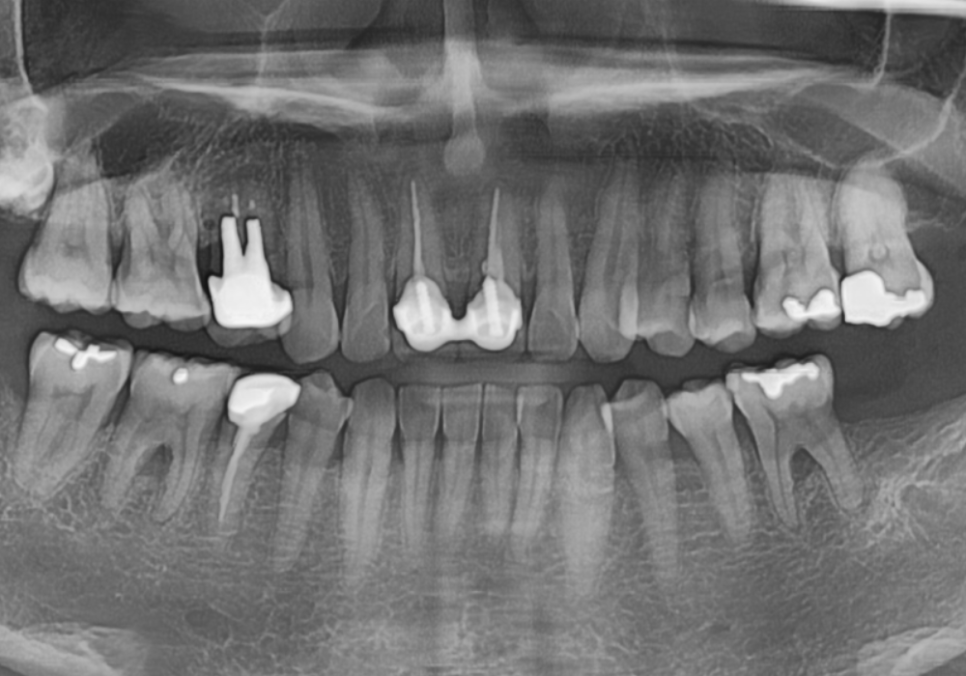

방사선 사진을 확인해 보니

예상보다 상태가 좋지 않았습니다.

신경치료 후 포스트(금속 기둥)까지

해둔 상태였고 뿌리 쪽으로

2차 충치가 상당히 진행되었습니다.

포스트까지 해두셨다는 건

크라운을 제작 당시,

치아 손상이 컸다는 것을 뜻하는데요.

250513

치아를 흔들어보니

안쪽이 많이 삭아,

약간의 흔들림까지 있었죠.

크라운을 제거하면 치아가 부러질

가능성이 높은 상태였기 때문에

재치료보다는 발치 후 임플란트가

더 안전하고 오래 쓰실 수 있는 방법이라고

환자분께 솔직하게 상태를 설명드렸습니다.